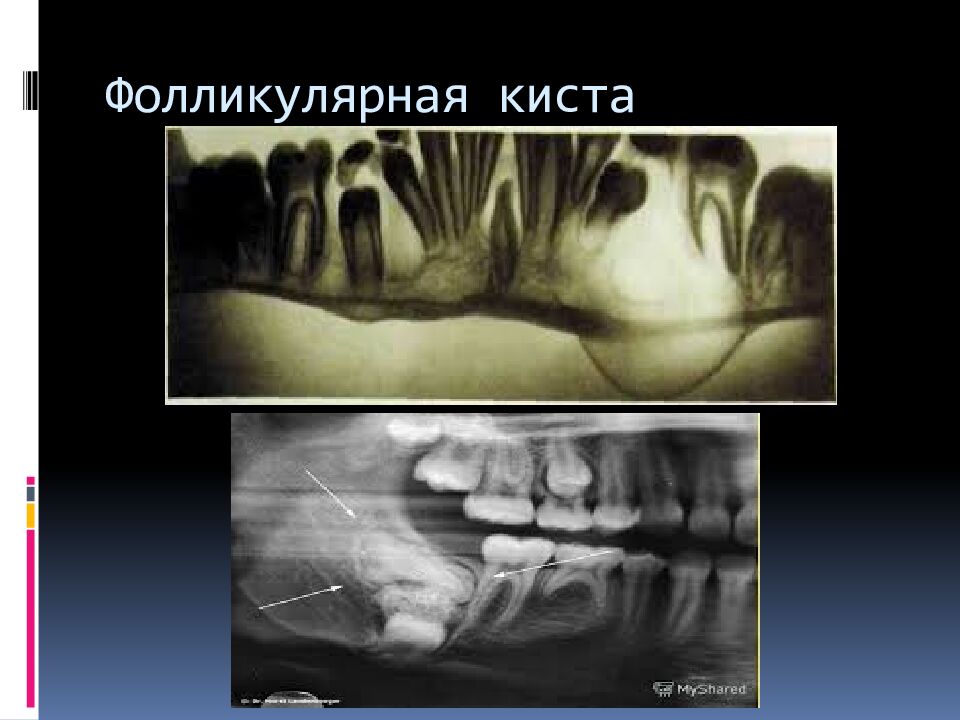

• Фолликулярная киста

1. Эпителиальные: Одонтогенные кисты: первичная киста (примордиальная кератокиста ); киста прорезывания; пародентальная ( периодонтальная ); десневая ; зубосодержащая ; фолликулярная; корневая ( радикулярная ). Неодонтогенные кисты: киста резцового канала ( носонёбного протока) глобуломаксиллярная киста ( фиссуральная ); киста носогубная ( носоальвеолярная, преддверия полости рта); холестеатома.